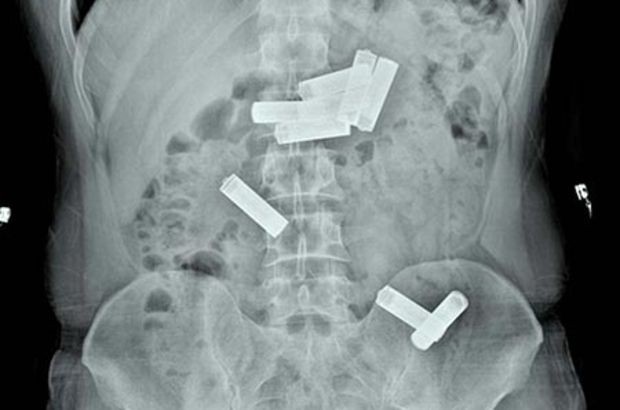

Acil serviste muayenesi yapıldıktan sonra çekilen röntgende D.K.'nin midesinde 8 kalem pil olduğu saptanınca Endoskopi Servisi'ne sevk edildi. Gastroenteroloji uzmanı doktor Ahmet Yağbasan başkanlığındaki ekip, yaptığı çalışma ile D.K.'nin midesindeki pillerin birisini çıkardı.

Uzmanlar, mahkumun midesindeki diğer 7 pilin müdahale yapılarak çıkarılmasının dokulara zarar vereceğini belirleyince takip altında doğal yollardan çıkarılması kararını verdi. Bunun üzerine servise yatırılan D.K., 2 gün sonra midesindeki pilleri doğal yollarla vücudundan çıkardı. Tedavisinin ardından taburcu edilen mahkum yeniden cezaevine gönderilirken, doktor Ahmet Yağbasan karşılaştığı manzaranın kendilerini şaşırttığını söyledi. İğne, boncuk ve bozuk para yutan hastalarla sıkça karşılaştıklarını ancak ilk kez midesinde 8 kalem pil olan bir vaka gördüklerini anlatan Ahmet Yağbasan, şöyle dedi:

"Vaka bize cezaevinden karın ağrısı şikayetiyle getirildi. Acil serviste çekilen röntgende midesinde kalem pillerin olduğunu belirledik. Bunun üzerine hastayı endoskopi ünitesine aldık. Midede 8 pil olduğunu gördük ve bunları özel aletlerle çıkarmayı denedik. Yaptığımız müdahale ile birini çıkardık ama diğerlerinin pozisyonu uygun olmadığı için çıkaramadık. Pillerin içindeki kimyasal maddelerden dolayı doku hasarına yol açabileceğine kanaat getirerek, hastanın diğer 7 pili takip altında doğal yollardan çıkarmasını kararlaştırdık. Serviste yatan hastamız 2 gün sonra pilleri doğal yollardan çıkarmış oldu."

Gaziantep'te, işlediği bir suç nedeniyle hükümlü olarak cezaevinde kalan ve rahatsızlanınca hastaneye kaldırılan mahkumun midesinden 8 kalem pil çıktı.